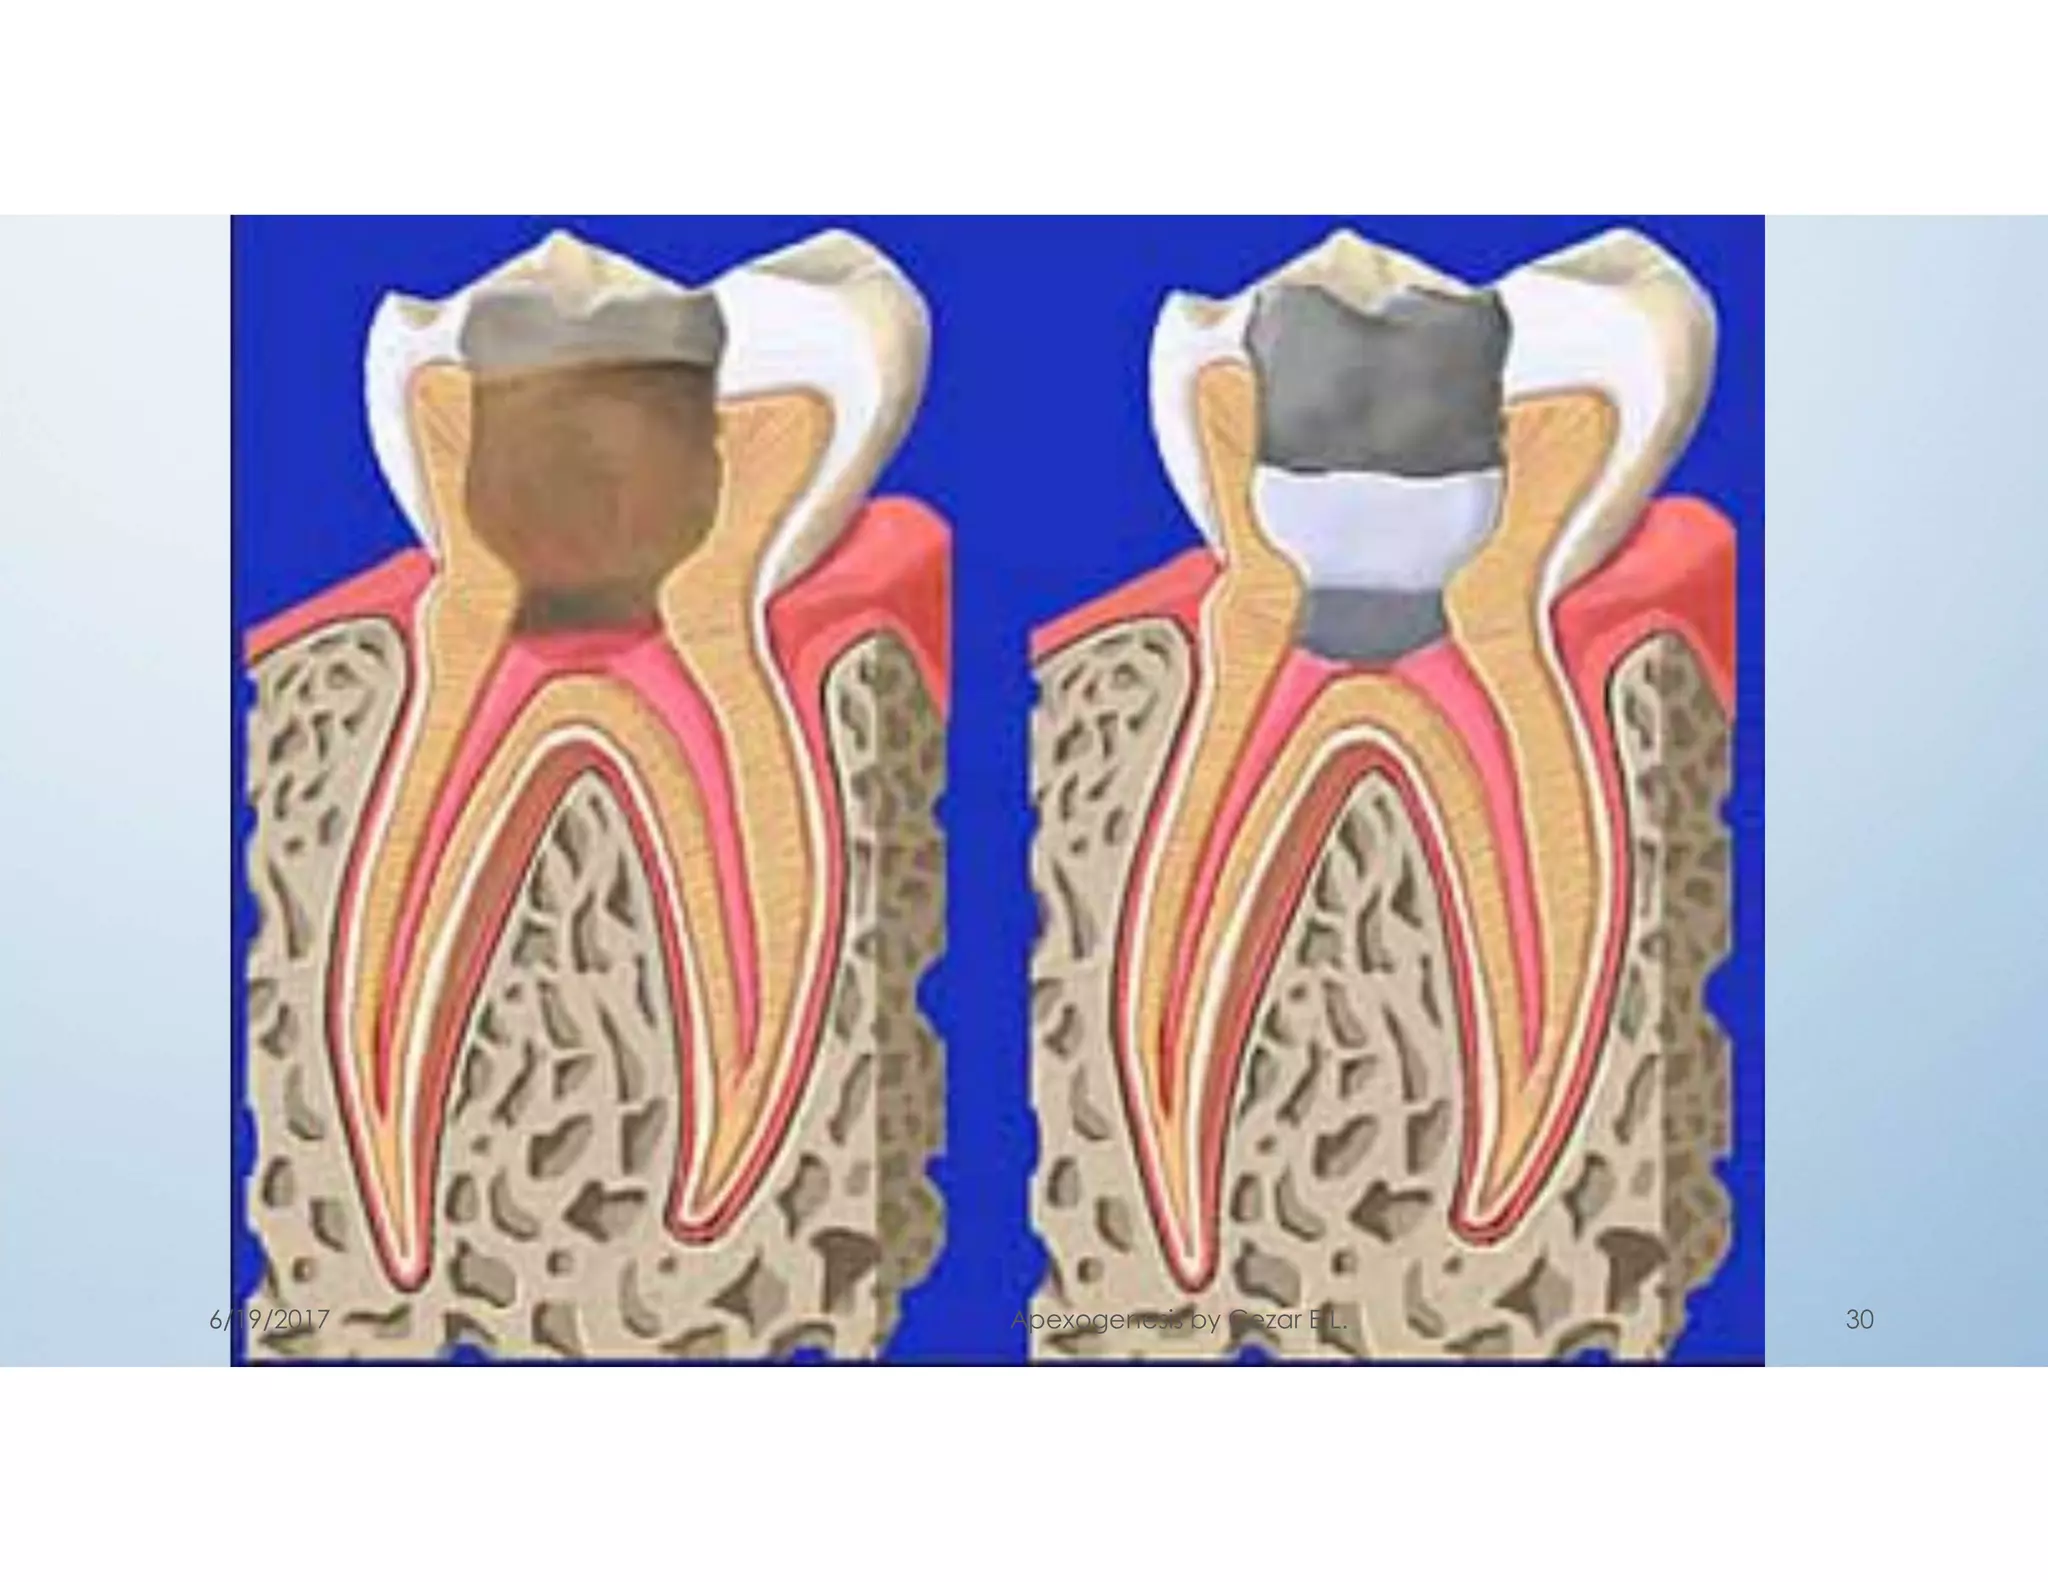

3- Pulpotomy

Total removal of coronal pulp tissue

Partial removal of coronal pulp tissue =Cvek

defined as a procedure in which a portion of

exposed vital pulp is surgically removed as a

means of preserving the vitality and function of the

remaining radicular portion. “so root development

continues”